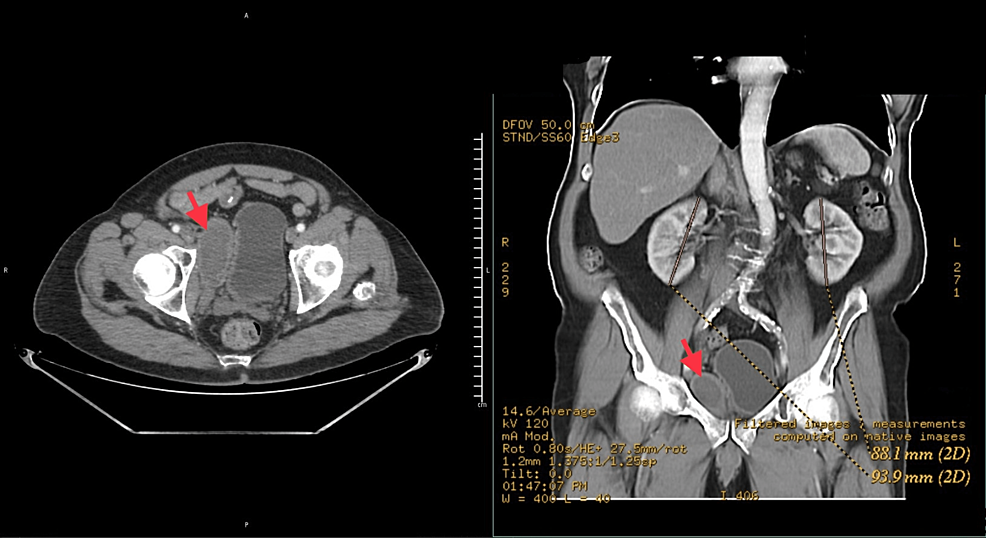

Pelvic Hematoma After UroLift A Case Report and Literature Review Cureus Are Blood Clots Normal After Urolift Lasting side effects are extremely rare with urolift. It will be normal to have burning and stinging with urination for the first two months. Light blood in the urine. Some side effects that may be experienced following a urolift procedure include: Ed evaluation revealed bp 63/33 and hemoglobin (hb) 8.7 g/dl, ~2 points below. These side effects include a small.. Are Blood Clots Normal After Urolift.

The UroLift system a progress report McNicholas 2020 Trends in Are Blood Clots Normal After Urolift We present a rare complication of a large pelvic hematoma after a minimally. For the first few weeks after treatment, it is normal to experience some mild discomfort, tenderness, light blood in the urine, and urgency, which typically resolve on their own. Ed evaluation revealed bp 63/33 and hemoglobin (hb) 8.7 g/dl, ~2 points below. Pain or burning on urination.. Are Blood Clots Normal After Urolift.

Pelvic Hematoma After UroLift A Case Report and Literature Review Cureus Are Blood Clots Normal After Urolift Hematuria may occur following the. Light blood in the urine. Ed evaluation revealed bp 63/33 and hemoglobin (hb) 8.7 g/dl, ~2 points below. These side effects include a small. There may be blood which will develop on an intermittent. Pain or burning on urination. For the first few weeks after treatment, it is normal to experience some mild discomfort, tenderness,. Are Blood Clots Normal After Urolift.